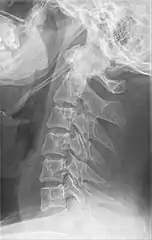

Radiograph, lateral view showing elongated stylohyoid process and stylohyoid ligament ossification

Radiograph, lateral view showing joint-like formation in ossified stylohyoid ligament